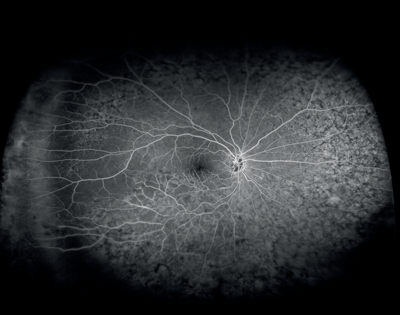

A comparative evaluation of phase-variance OCT (PV-OCT) and FA in normal individuals and patients with age-related macular degeneration (AMD) and diabetic retinopathy (DR) found that phase-variance OCT, which provides volumetric imaging of the retinal vasculature, yields high-resolution imaging of the retinal and choroidal microvasculature that compares well with FA, the current gold standard for retinovascular imaging [2]. Investigators reported that the choriocapillaris was imaged with better resolution of microvascular detail using PV-OCT. Ocular coherence angiography captures retinal vascular changes using split-spectrum amplitude decorrelation angiography [SSADA) to dissect layers of vessels in the retina, and may provide relevant information on the pathophysiology of abnormalities of the retinal vasculature [3].

Figures 8 and 9: Case examples from clinical sites: choroidal neovascularisation associated with AMD visualised using fluorescein angiography and optical coherence tomography angiography (images courtesy of Optovue, Inc, CA, USA).